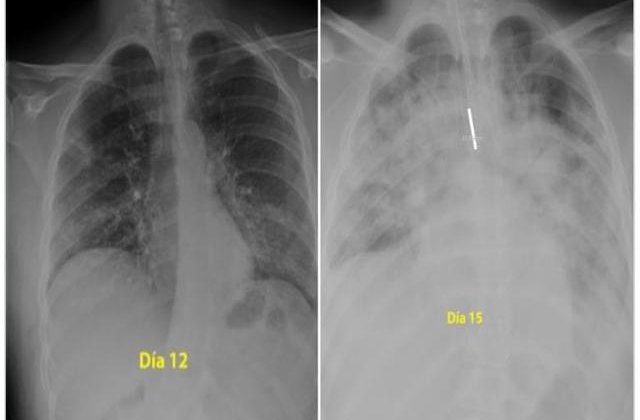

Radiografia unei persoane infectate cu Covid-19 arată efectul dramatic pe care îl are virusul asupra plămânilor pacienților.

Un pneumolog din Spania a postat pe Twitter radiografia unui pacient în vârstă de 28 de ani care a făcut o formă gravă de coronavirus. Radiografiile sunt realizate la doar trei zile distanță și arată gradul de degradare a plămânilor.

"Pentru cei care se cred invincibili și continuă să iasă în parc, ignorând ordinele de a ramâne în casă, acestea sunt radiografiile unui tânăr de 28 de ani intubat la Terapie Intensivă în spitalul meu cu coronavirus. Indiciu: plămânii sunt negri, albul este pneumonie, "a scris pneumologul pe rețeaua de socializare.

Para los que se creen inmortales y siguen saliendo al parque sin hacer caso a la orden de permanecer en domicilio, estas son las radiografías de un chico de 28 años intubado en la UCI en mi hospital por #coronavirus. Pista: los pulmones es lo negro, lo blanco es neumonía pic.twitter.com/HsWOj43EVv